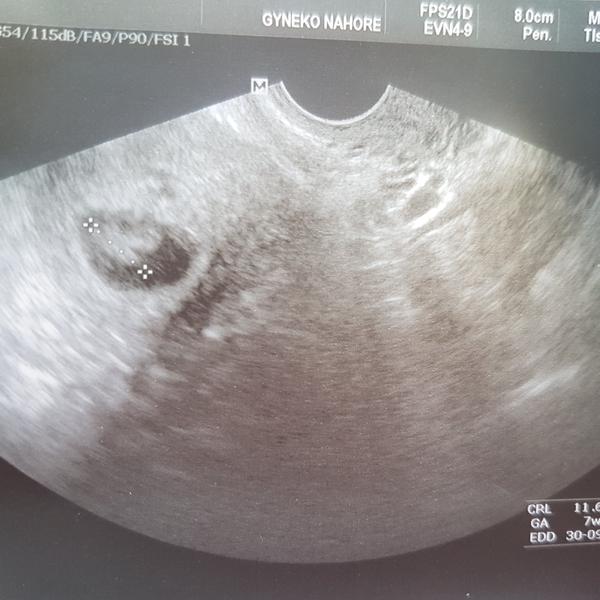

Tak co, máte "dvě čárky"? - termín porodu v září 2019

Krásný!! Já už chci taky ultrazvuk, holky jsem dojatá.. ty hormony 😀